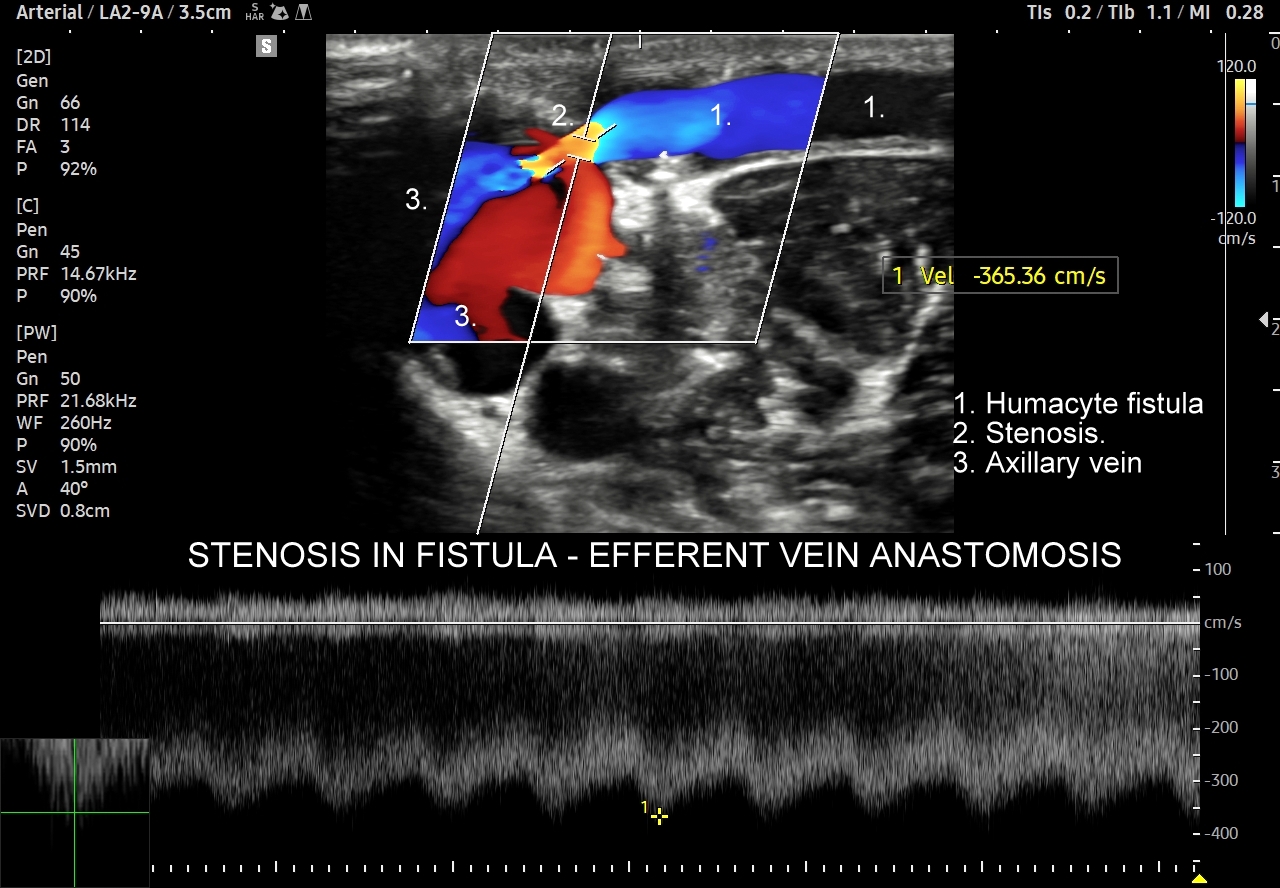

48. Ocena przetok dializacyjnych.

- Badanie USG przetok dializacyjnych.

Kurs USG Doppler był dla mnie bardzo wartościowy i realnie przydatny w codziennej praktyce internisty i nefrologa. Dużym plusem było to, że nie ograniczał się do podstaw, ale w dużej mierze rozbudowywał znane już zagadnienia i wyraźnie poszerzał wiedzę, szczególnie w obszarach, z którymi na co dzień spotykam się na oddziale i w stacji dializ. Najbardziej skorzystałem z części dotyczącej USG Doppler nerek i naczyń nerkowych – hemodynamiki, zwężeń tętnic nerkowych oraz zaburzeń odpływu żylnego. Te tematy są często problematyczne w praktyce internistycznej i nefrologicznej, a na kursie zostały omówione w sposób jasny i bardzo „życiowy”. Równie przydatna była ocena przetok dializacyjnych, zarówno pod kątem techniki badania, jak i interpretacji przepływów i powikłań, co zdecydowanie ułatwia codzienną pracę z pacjentami hemodializowanymi. Całość kursu miała wyraźnie praktyczny charakter i pomogła mi uporządkować oraz pogłębić wiedzę, którą można od razu wykorzystać przy pacjencie. To szkolenie, które faktycznie podnosi komfort pracy z USG Doppler i daje większą pewność w podejmowaniu decyzji klinicznych. Zdecydowanie polecam je internistom i nefrologom!

Kompleksowy kurs USG Doppler naczyń, pomaga ugruntować posiadaną wiedzę, rozwiać wątpliwości na temat obrazu, żeby go należycie zrozumieć oraz zobaczyć ciekawe przypadki. Szczególnie wartościową częścią kursu była ocena przetoki Humacyte, bo bardzo niewielu jest pacjentów z tą przetoką.

Maciej Zębik | Radiolog | Wrocław